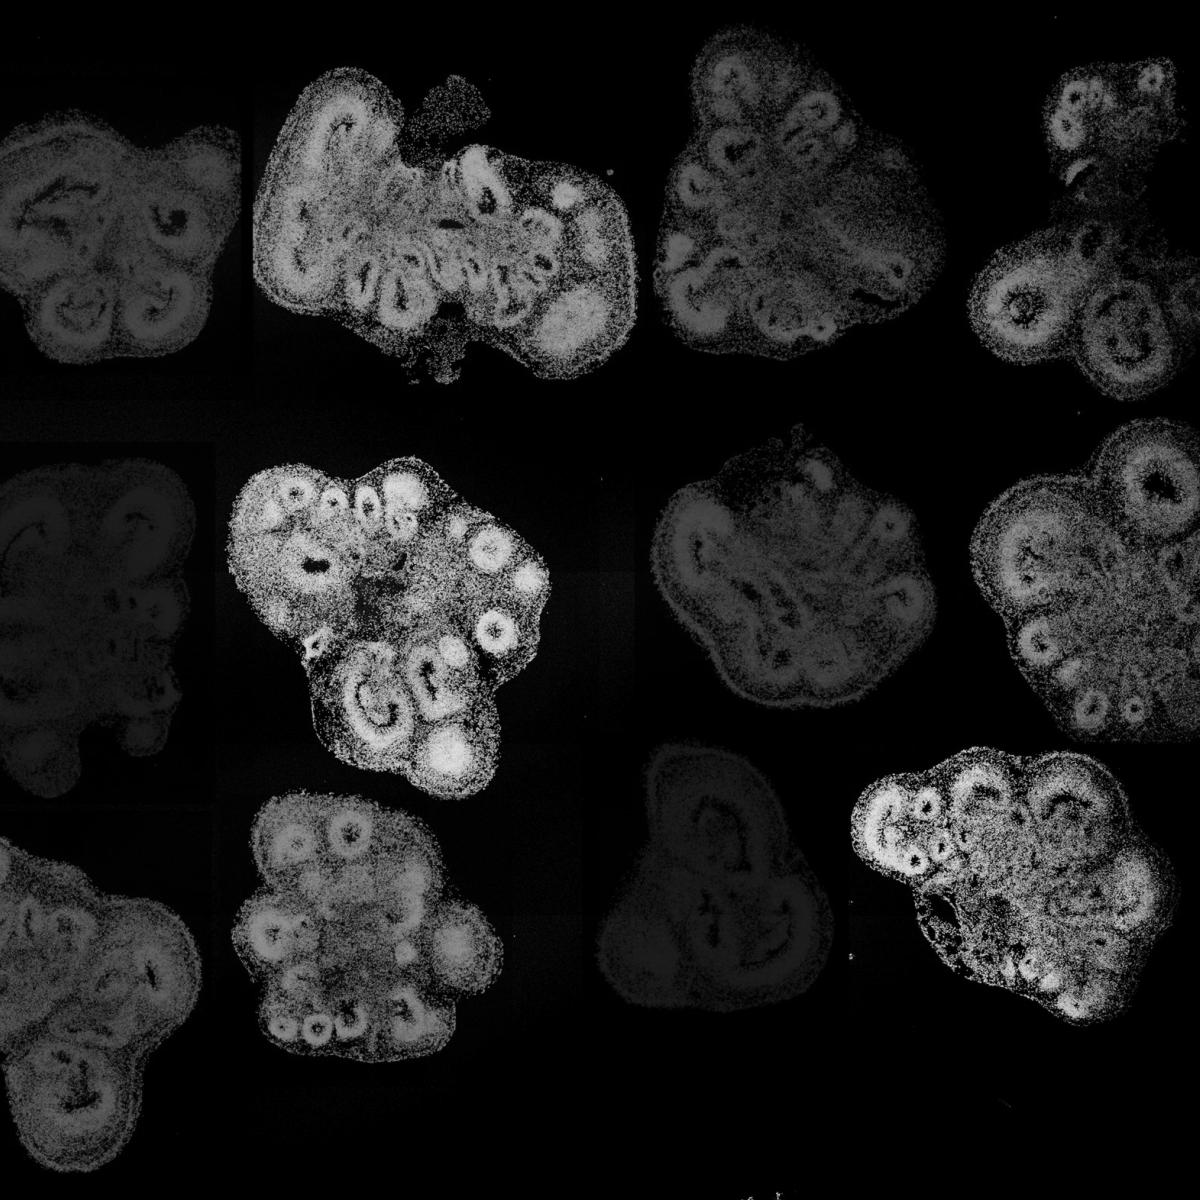

Most recently, he has been leveraging his understanding of these developmental processes to create simplified models of brain and spinal cord tissues from human embryonic and induced pluripotent stem cells using 3D organoid approaches. These technologies offer an unprecedented opportunity to investigate features of human development and pathologies that cannot be easily recapitulated in model organisms such as mice.

Utilizing these 3D brain organoids, Novitch models the formation and function of human neural circuits to better understand the basis of neurodevelopmental and neuropsychiatric disorders, as well as the root causes of neurodegenerative diseases such as spinal muscular atrophy and amyotrophic lateral sclerosis. He seeks to use this experimental platform for drug discovery and the development of cellular therapies to repair the injured or diseased nervous system.